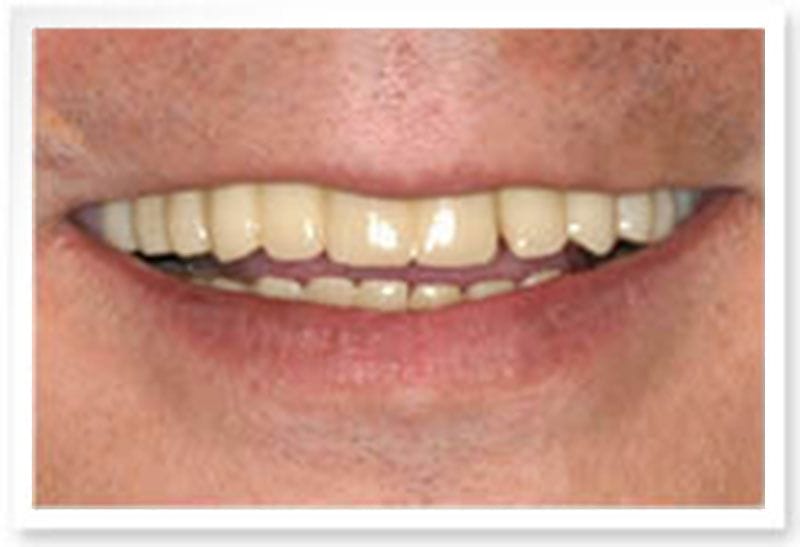

治療後

治療後-口外正面